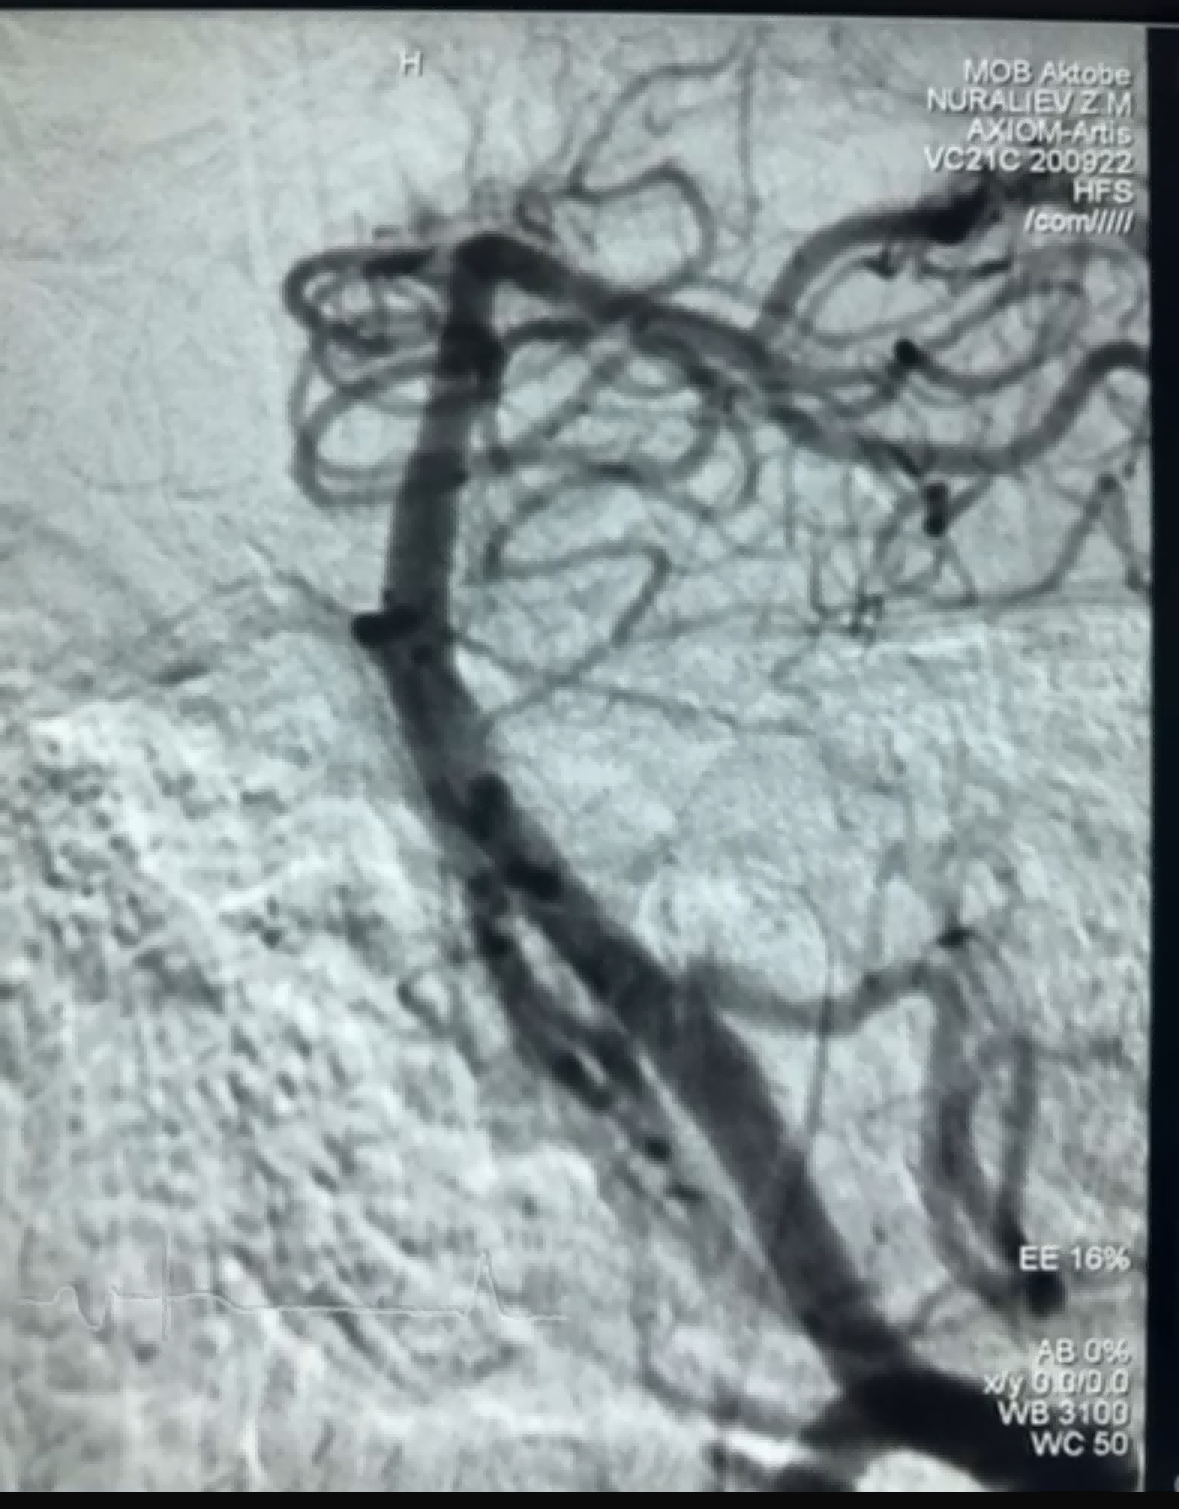

Nylig var det et vellykket trombektomitilfelle ved bruk av Dredger Stent Retriever fra NeuroSafe Medical Co., Ltd. Dredger Stent Retriever har en ikke-invasiv myk spiss, som i stor grad reduserer risikoen for intimal skade, og har et unikt spesialformet hull design som fanger opp blodpropp hovedsakelig ved å klemme gapet endringer.